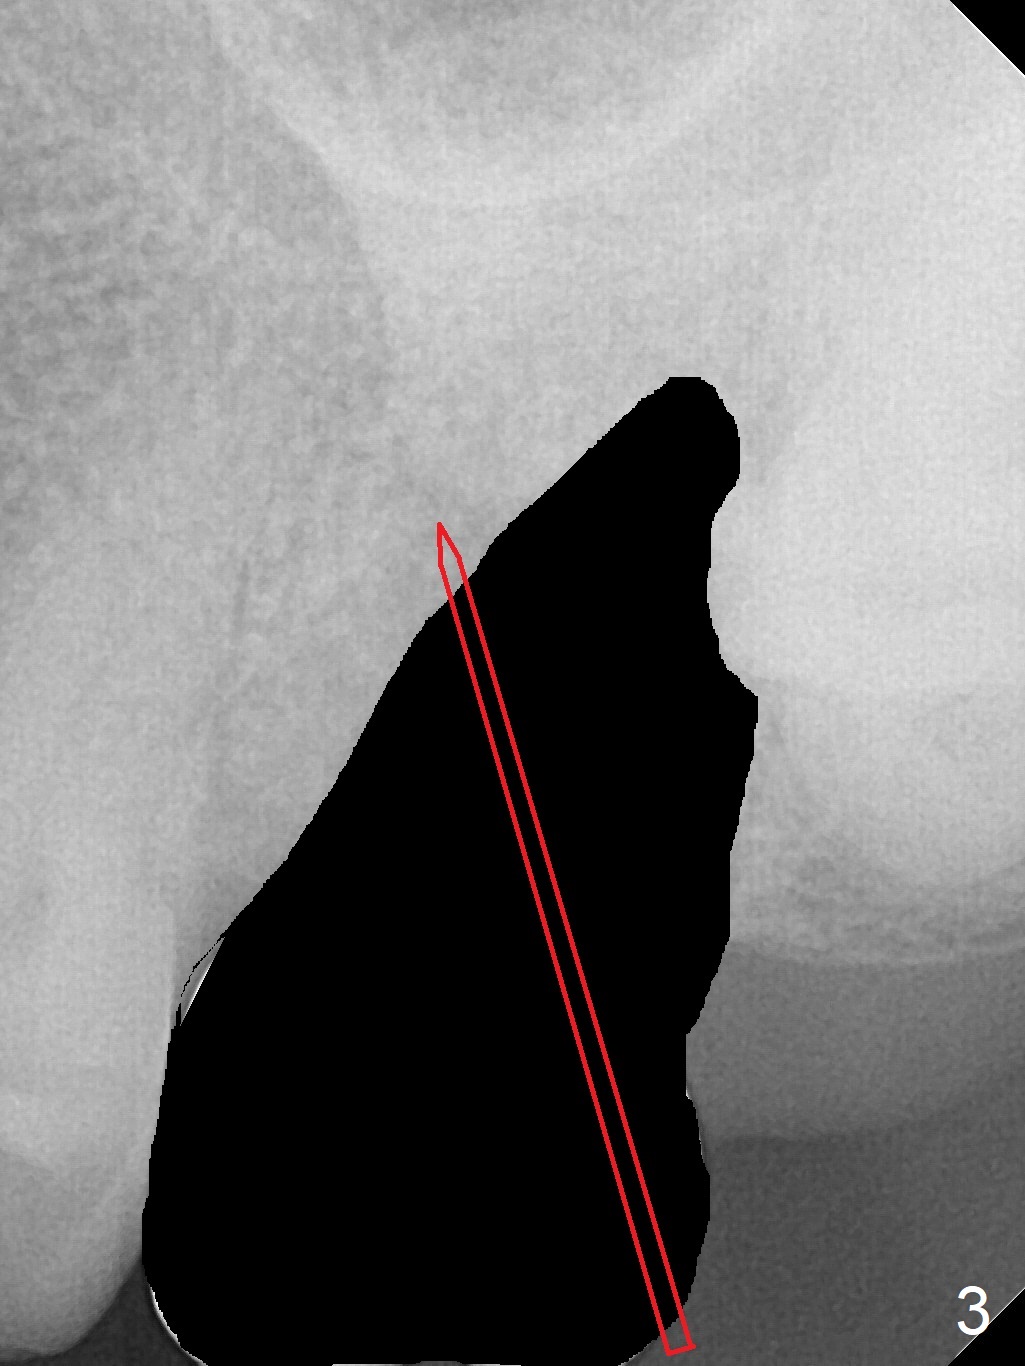

Osteotomy in Mesial Slope A 64-year-old woman will return for extraction/implant for the upper left 2nd molar with a fistula (Fig.1). Since the roots deviate distal (Fig.2 after extraction), initiate osteotomy in the apical 1/3 of the mesial slope with 1.5 mm drill (Fig.3). Once the lamina dura is penetrated, change trajectory (Fig.4) and extend depth for 15 mm (gingival level). After use of 2 mm drill, insert marked parallel pin for PA. The final implant as well as abutment is shown in Fig.5. Return to